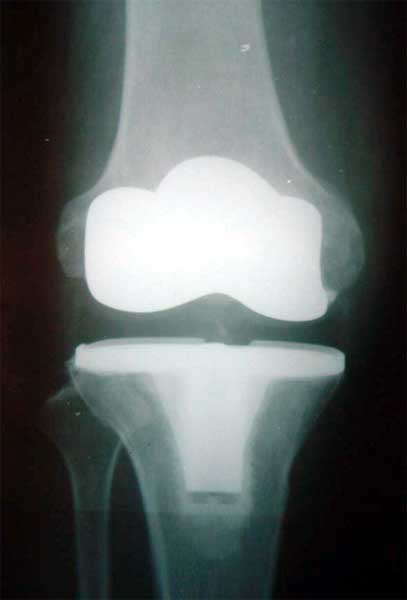

1、标准的放射影响检查,以获得肩胛盂骨性结构的数量、质量及方向,以及肱骨头的大小、形状。

2、使用模板在术前X片上画出截骨线和假体位置